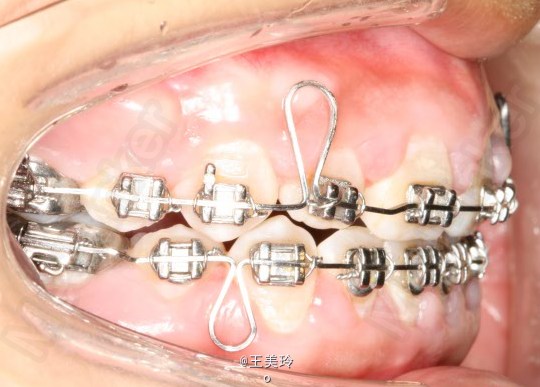

主诉:面突求矫治 既往史:无矫治史,无牙科治疗史,无外伤史,无过敏史,无口腔不良习惯,无家族遗传史 口腔检查:恒牙列,A7-B7;C7-D7。个别牙齿不齐 尖牙磨牙I类关系轻度深覆合深覆盖 下颌中线右偏约2mm 双颌前突,突面型 关节无弹响无压痛

诊断:安氏I类双颌前突 矫治计划 1.MBT矫治技术 2.拔牙矫治,拔A4B4C4D4 3.闭隙曲,J勾内收前牙 4.矫治结束后尖牙,磨牙,覆合覆盖正常 5.面型有所改善